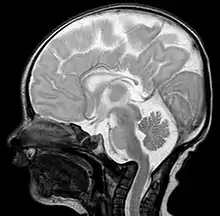

Basilar invagination in an infant with Wolf–Hirschhorn syndrome.